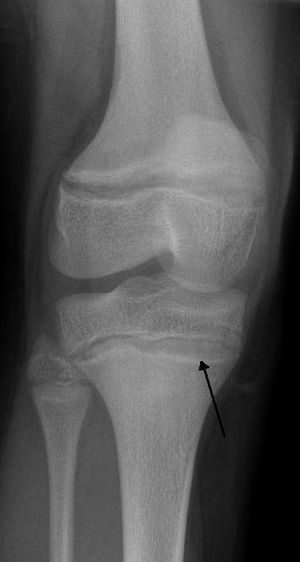

An X ray demonstrating the characteristic finding of lead poisoning, dense metaphyseal lines.